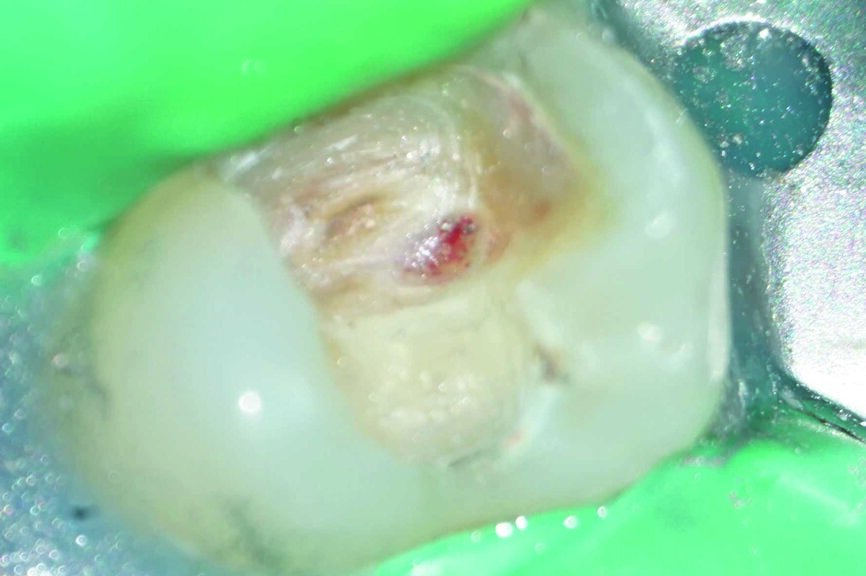

Ein 24-jähriger Patient kam mit vorübergehenden, provozierten Zahnschmerzen an Zahn #19 in die Zahnklinik (Abb. 1). Die Diagnose lautete reversible Pulpitis. Die Zahnfäule wurde unter kompletter Isolation entfernt, wobei es zweimal zur Freilegung der Pulpa mit minimalen Blutungen kam (Abb. 2). Die Blutungen wurden gestoppt, indem 10 Sekunden lang ein mit steriler Salzlösung getränkter Wattebausch auf die Stelle gedrückt wurde. Die Mundhöhle wurde mit 2,5% Natriumhypochlorit desinfiziert (Abb. 3), anschliessend wurde weißes MTA (Produits Dentaires) als Mittel zur unmittelbaren Pulpa-Überkappung eingesetzt (Abb. 4). Um sicherzustellen, dass das MTA korrekt eingesetzt wurde, kam das MAP-System für Dentalmaterialien (Produits Dentaires) zur Anwendung. Mit diesem System kann der Klinikarzt das Material exakt an der Expositionsstelle anbringen. Somit wird eine Verunreinigung der Dentinwände verhindert, die mit der Zeit eine Pigmentierung infolge des verwendeten Materials aufweisen könnten (Abb. 5 und 6). Sobald das MTA auf die Expositionsstellen der Pulpa und die tieferliegenden Teile des Pulpakammerdachs aufgetragen wurde, kam eine lichthärtende Kalziumhydroxidpaste zum Einsatz, um das Material zu schützen (Abb. 7), das Klebeverfahren durchführen und die abschliessende Zahnreparatur in derselben Sitzung vornehmen zu können (Abb. 8 und 9). Sieben Tage nach dem Verfahren war der Patient komplett symptomfrei und der Zahn reagierte normal auf Sensitivitätstests. In solchen klinischen Situationen ist davon auszugehen, dass zwischen sechs und neun Monaten nach dem Verfahren die Bildung von Kalkgewebe unter dem Überkappungsmaterial in Röntgenaufnahmen nachgewiesen werden kann. (7)